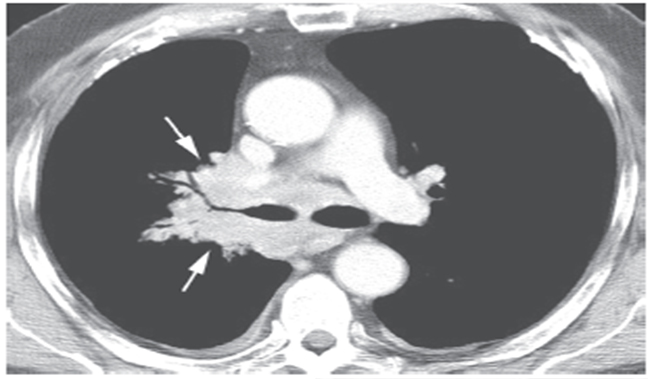

图17 石棉暴露后的右肺门肿瘤

A. 胸片显示边界不清的右肺门肿块(箭头),为典型的起源于肺门的肿瘤,可见石棉暴露后引起的胸膜增厚和钙化; B. 大的、边界不清的右肺门肿块包绕致右肺上叶支气管狭窄,为典型的小细胞肺癌的征象